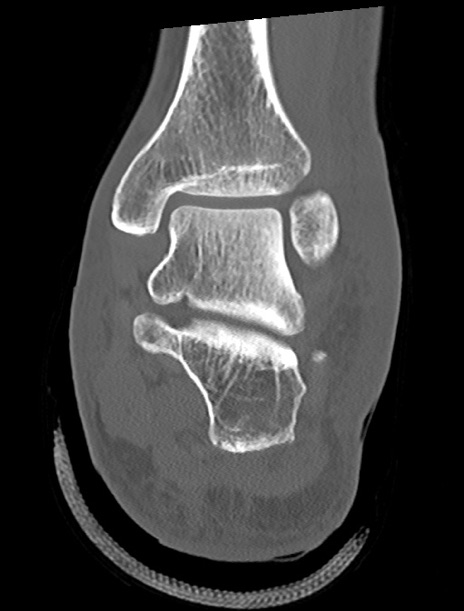

左足関節CT

矢状断像